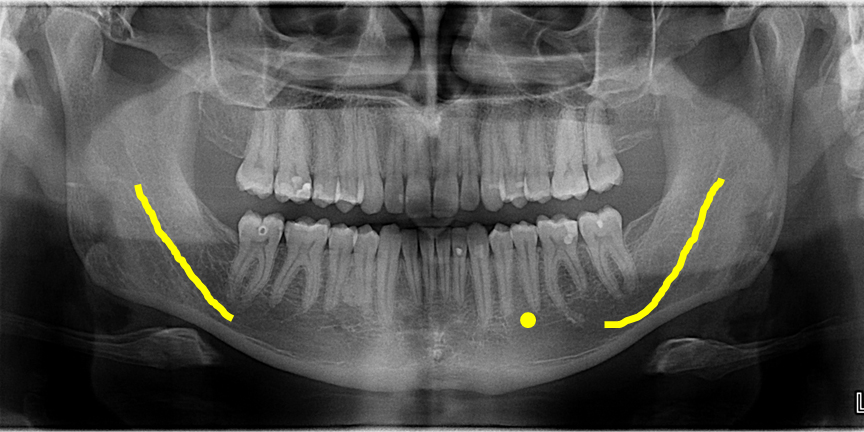

panoramic radiograph

panoramic